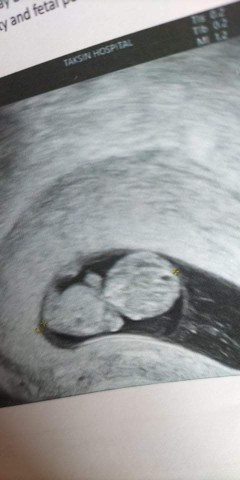

น้องเป็นแฝดตอนนี้อายุครรภ์3เดือนค่ะ